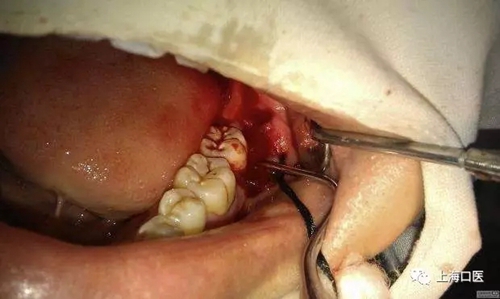

智齒拔除

分牙

我們拔牙時,能不用錘就不用,盡量減少創(chuàng)口,用錘分牙去阻的干槽癥發(fā)生率遠大于用手機分牙去阻的發(fā)生率,所用要多用手機,少用錘,用手機的時候也要注意,保護好牙周的軟組織,還有一點就是在分牙前一定要把手機中的潤滑油噴干凈,至少要讓手機先轉三分鐘,在很多拔牙術后,發(fā)生不明原因的疼痛,在一定程度上和手機殘留潤滑油有關,值得斟酌,且不管是否有關,只要我們做了工作,做好了細節(jié),自然可以減少患者疼痛的發(fā)生率的。細節(jié)決定成敗,一定要做好每一步工作,才能越趨于完美。